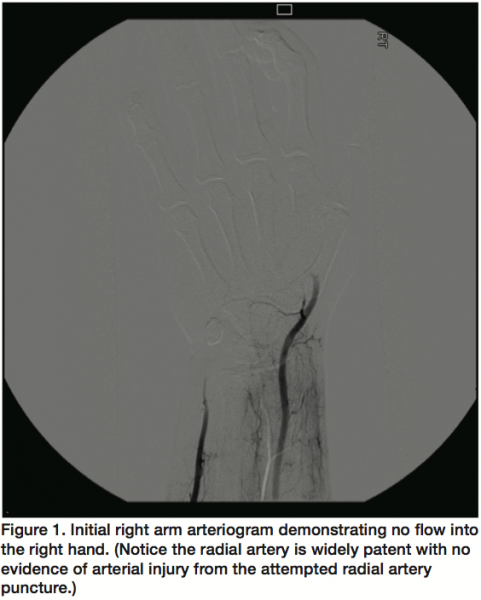

The patient’s right hand became dusky, bluish, cold, and pulseless. At the wrist, there were no Doppler signals in the distal ulna artery, distal radial artery, or the palmar arch. Interventional radiology was consulted for angiographic evaluation of the hand. Using standard interventional technique, a selective catheter was placed in the right subclavian artery from the right common femoral artery approach. An angiogram was performed demonstrating patent right subclavian and brachial arteries. There was no anomalous arterial anatomy of the radial, ulna, or median arteries. Focused images of the wrist and hand demonstrated distal occlusion of the radial and ulna artery with no flow into the deep or superficial palmar arch (Figure 1). First, a microcatheter was placed in the distal radial artery and intra-arterial TNK was delivered at .25 mg/H (2.5 mL/H) for an overnight infusion (approximately 12 H). Fibrinogen levels were monitored during the drug infusion. The next morning, the distal radial artery and deep palmar arch were patent. Subsequently, the microcatheter was then placed in the ulna artery and repeat overnight infusion (approximately 12 H) was performed at the same dose. The next morning, the distal ulna artery was patent with good flow into the superficial palmar arch. There were no bleeding complications during the two 12-hour thrombolytic infusions. Clinically, the hand was warm with brisk capillary refill to the digits suggesting widely patent vessels. A final right hand angiogram demonstrated patency of the ulna and radius to the hand (Figure 2). Overall, the patient improved clinically and was discharged in a few days following the procedure.